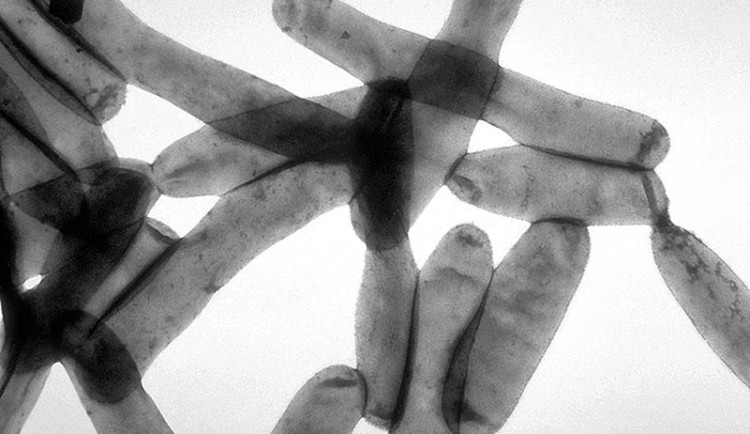

Legionella, kterou před několika dny likvidovali i v rozvodech teplé vody v Českých Budějovicích, může způsobit závažnou formu zápalu plic, takzvanou legionářskou nemoc. Méně závažný průběh mívá další onemocnění způsobené legionellou, a to pontiatická horečka, která napadá horní dýchací cesty.

Foto: CDC Public Health Image Library